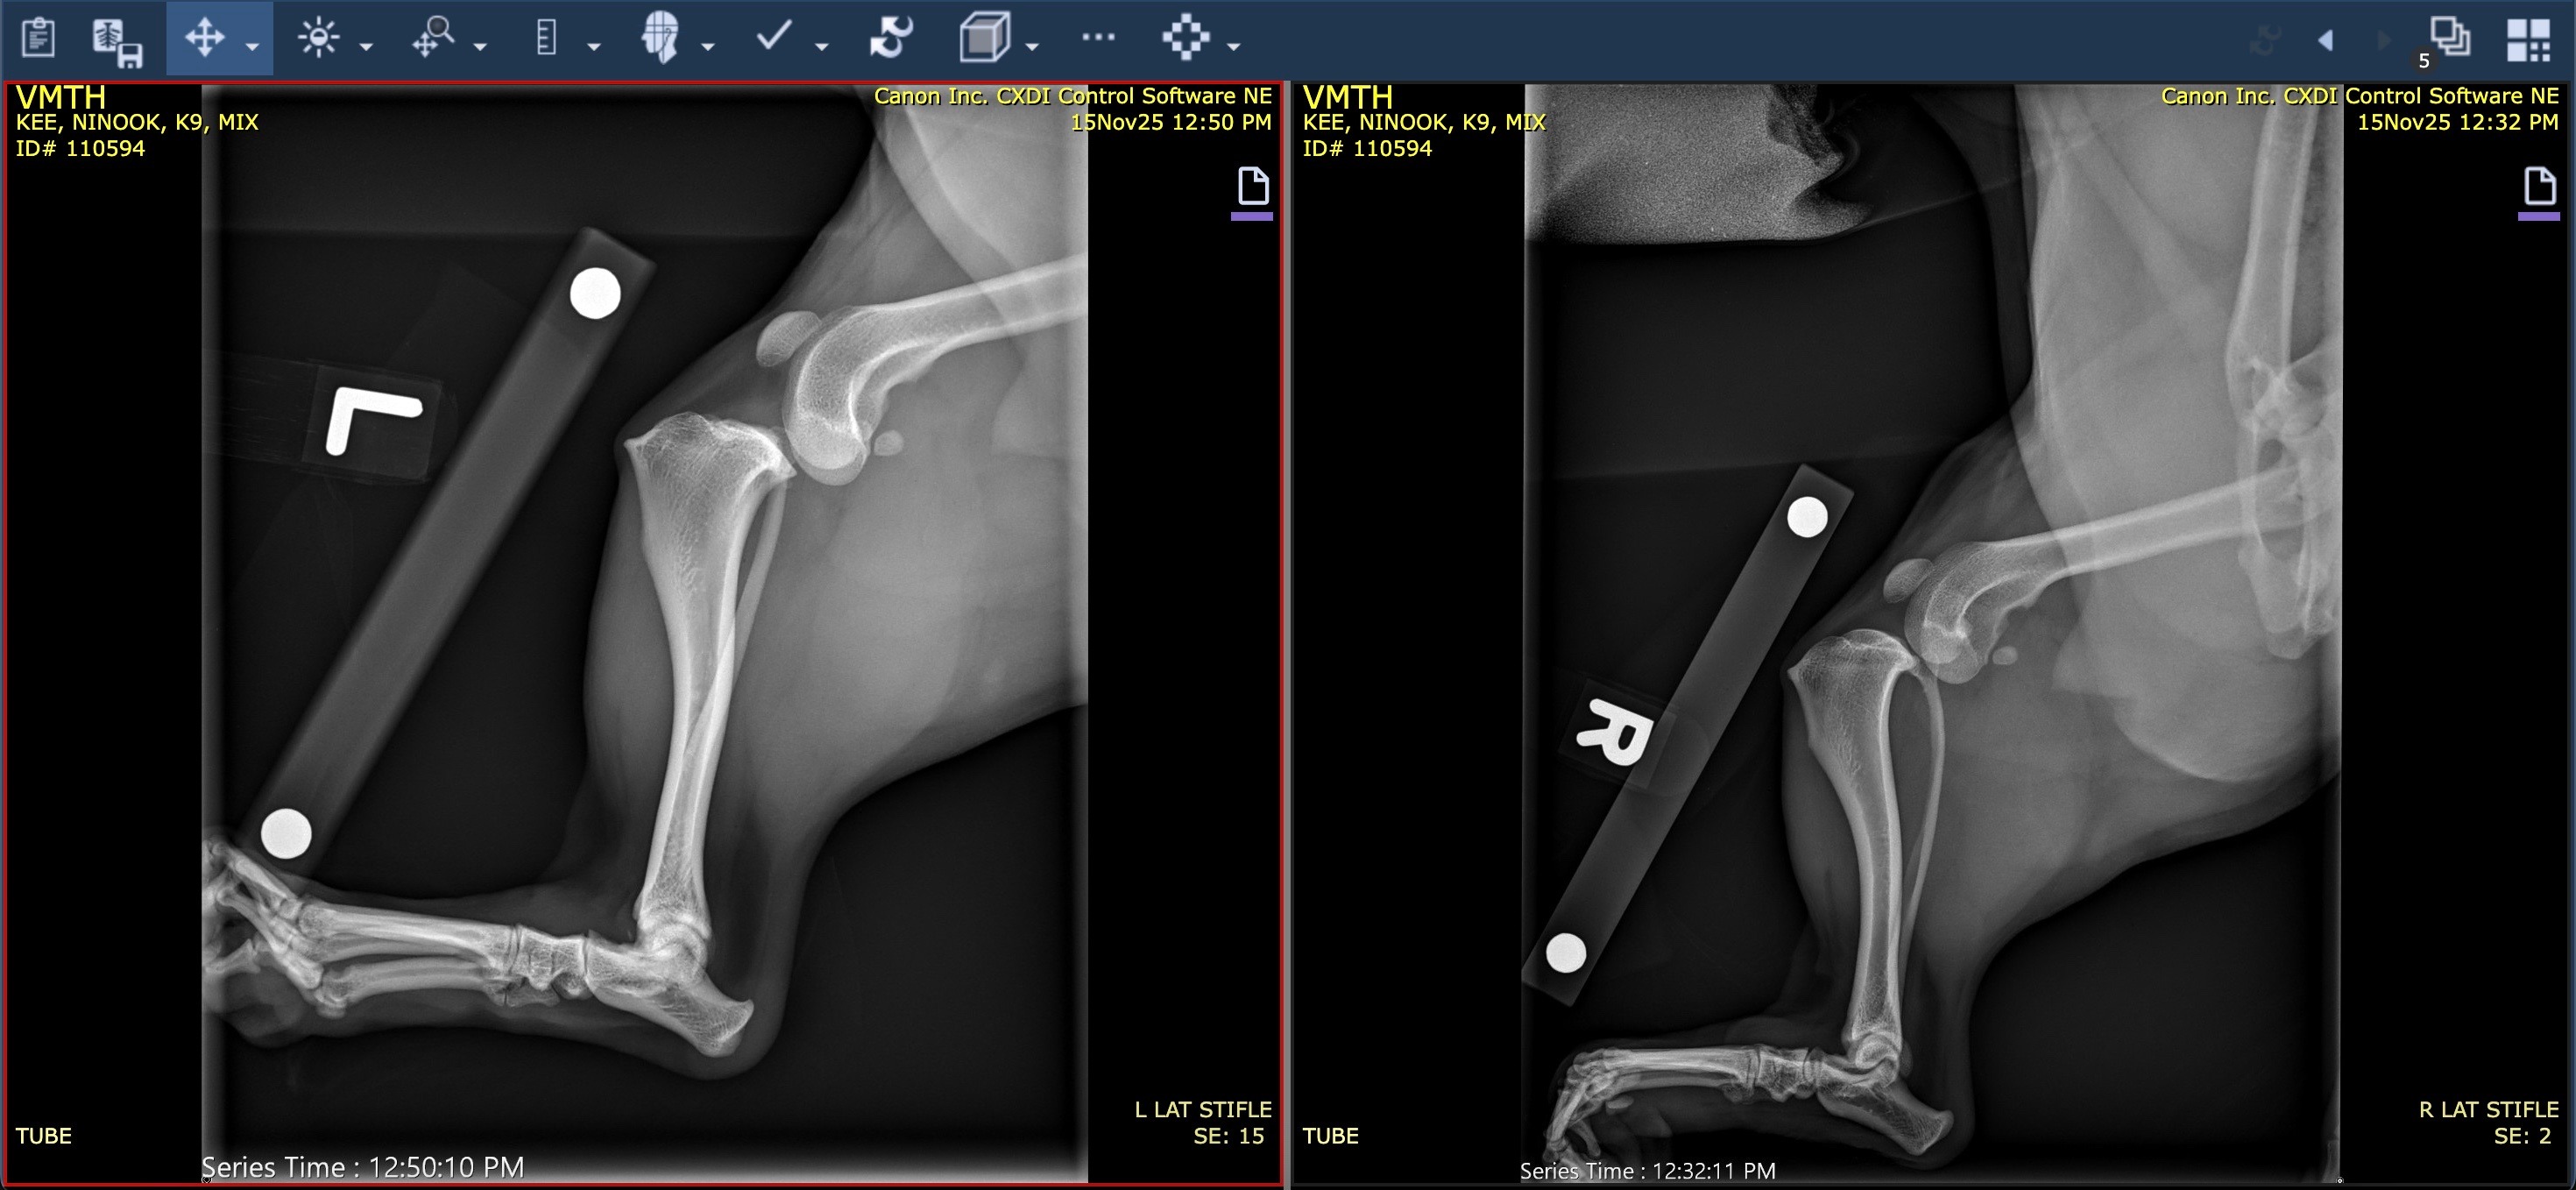

Just a few days ago, Ninook suddenly collapsed when I let her inside from playing in our yard. She was shaking, couldn’t stand, and both of her back legs dragged behind her. After rushing her to the ER twice over 48 hours and seeing a specialist, we learned the devastating news:

Ninook has ruptured both of her CCLs (the dog equivalent of ACLs in humans).

Both knees are unstable. She cannot stand or walk. She needs full assistance just to go to the bathroom. This is the opposite of who she is - a dog who loves walks, zoomies, exploring outside, and playing fetch. Seeing her unable to move is heartbreaking and completely uncharacteristic of my bright, happy girl.